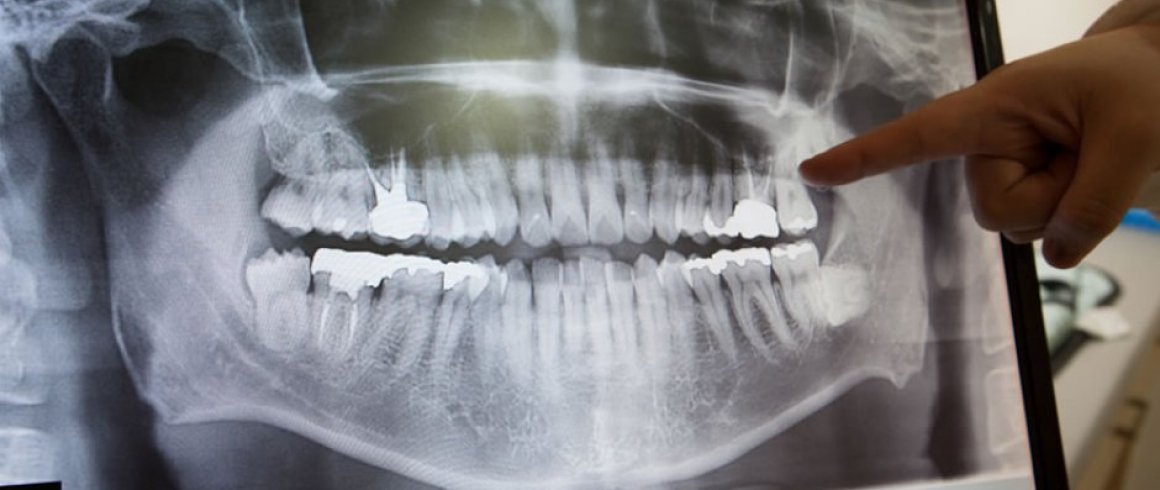

- Panorámica